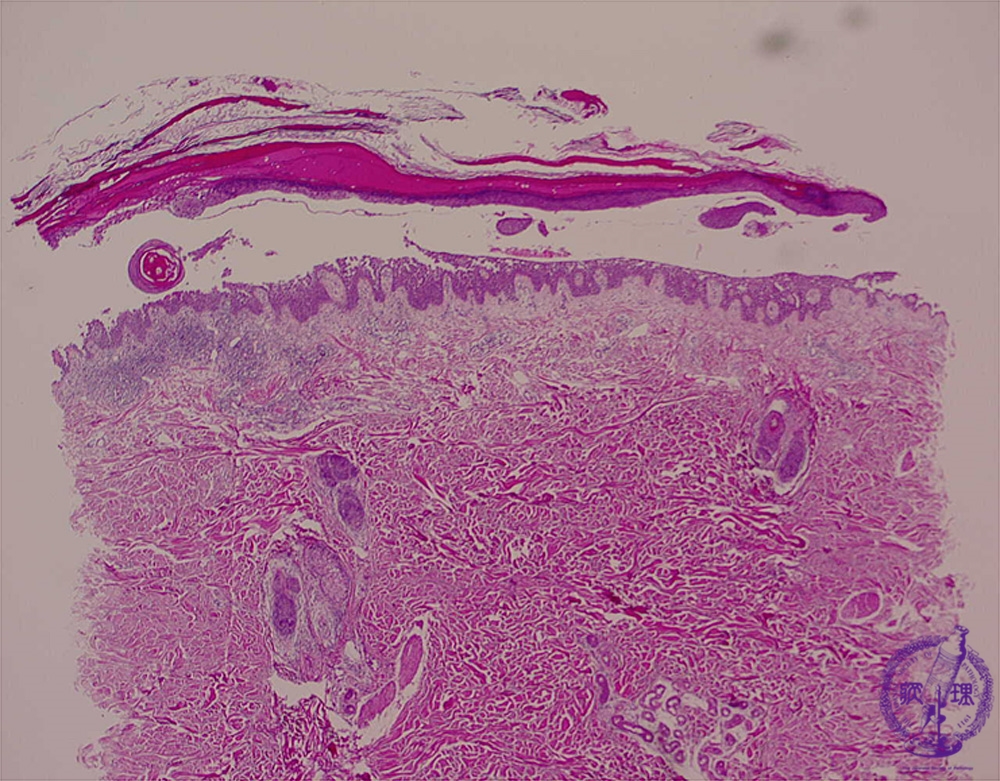

Microscopic image (pemphigus vulgaris): Intraepidermal separation corresponds to the bullae.

Compare with subepidermal separation of bullous pemphigoid.